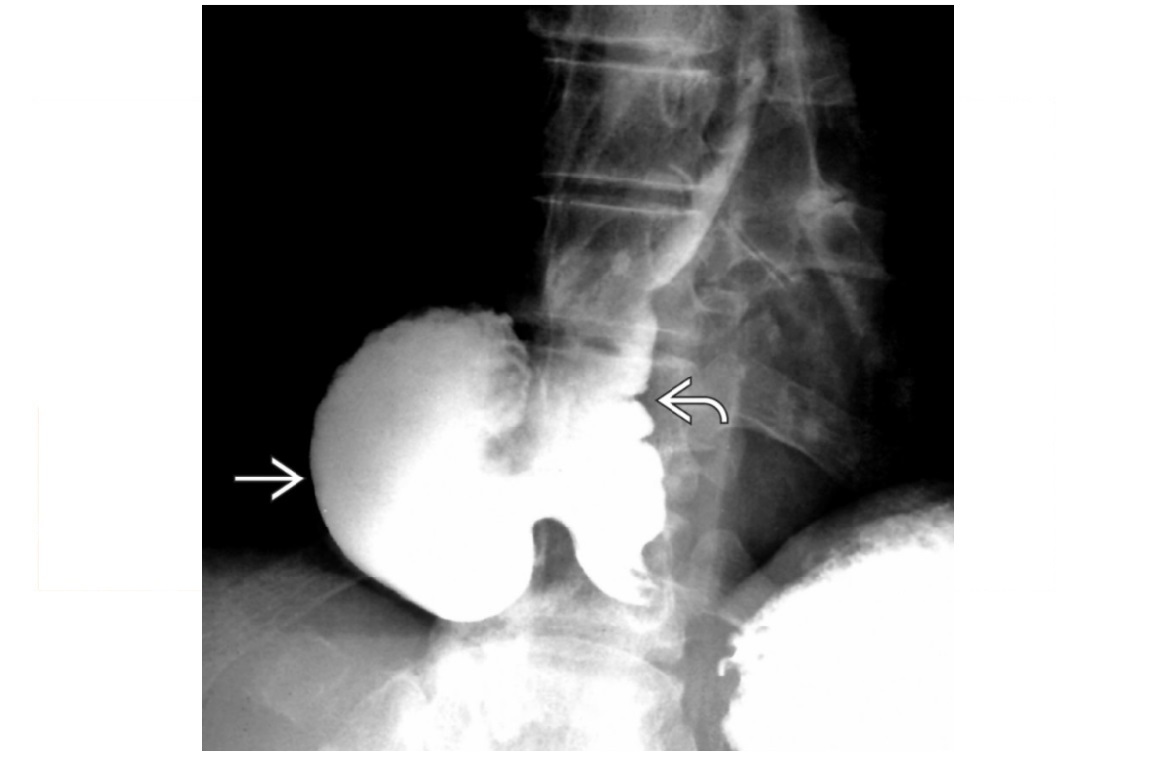

AAST grades for spleen

see image

AAST grades for kidneys